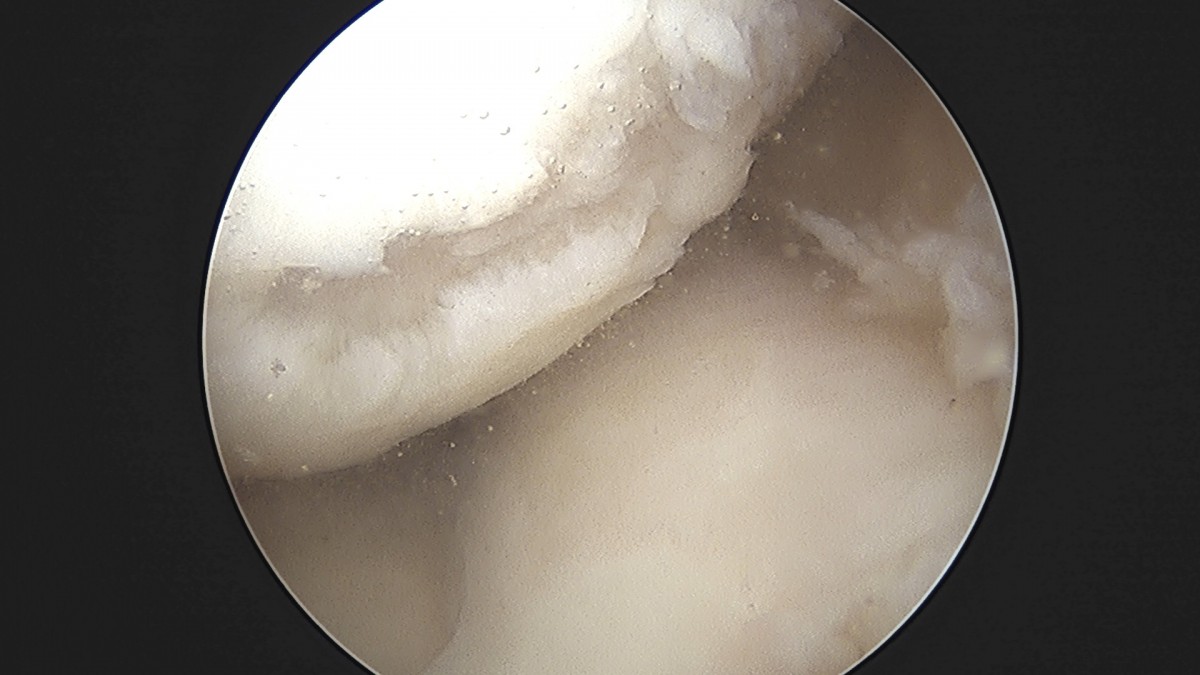

정지영원장님 무릎 반월상 연골판 절제술 이영O 환자

작성자 최고관리자 댓글 0건 조회 756회 작성일 25-09-16 16:56